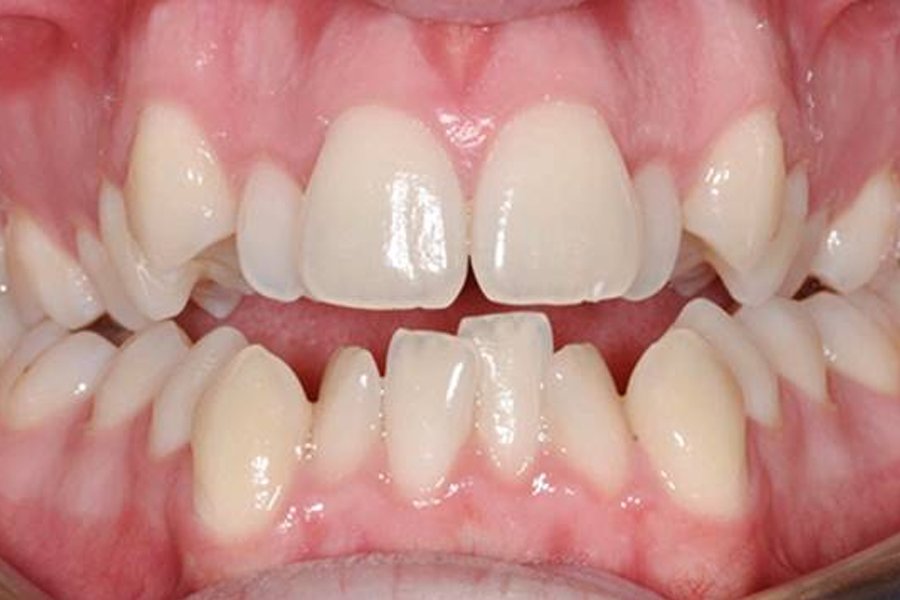

Những trường hợp lệch răng cần phải đến nha sĩChỉnh nha là một chuyên ngành của Răng Hàm Mặt, chuyên chẩn đoán, điều trị những lệch lạc răng và khuôn mặt.Chi tiết -